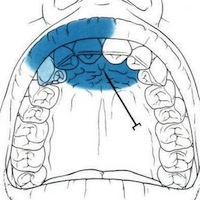

Les dentistes ont recours à l’anesthésie locale pour des extractions dentaires ou la pose d’un implant. En dermatologie, l’anesthésie locale est pratiquée lors de la résection d’un grain de beauté ou le traitement d’un ongle incarné.